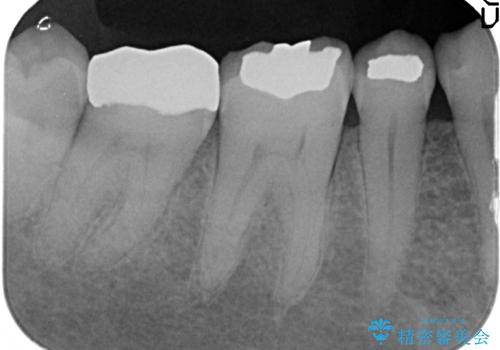

- 右下7の銀歯が外れてしまった方の症例です。

古い樹脂やカリエスを除去後、形を整え、オールセラミッククラウンによる補綴を行いました。

今回用いたオールセラミッククラウンはジルコニアフレームという白い素材の上にセラミックを盛っているため、審美性が非常に高いのが特徴です。

また、ジルコニアは人工ダイヤモンドの材料にも使われているほど高い強度を持っており、そのためオールセラミッククラウンは審美性だけでなく、奥歯やブリッジの補綴も可能とするクラウンです。